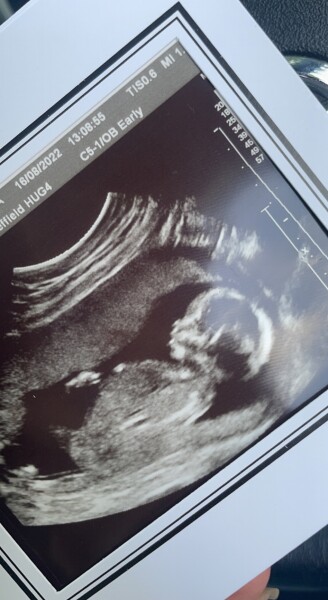

Just wanted to update babys doing fine I am now 17 weeks today heart beat was good and was a little wriggler and thumb sucker fingers crossed we’re going to be ok xx

FrankieBB · 22/05/2023 09:50

Here’s my clever little pumpkin she’s holding her self up allready so forward so clever and she’s only 4 and half months . She’s amazing I’m so glad

i didn’t take the second tablets she’s my 4th and I couldn’t imagine her not being here xx